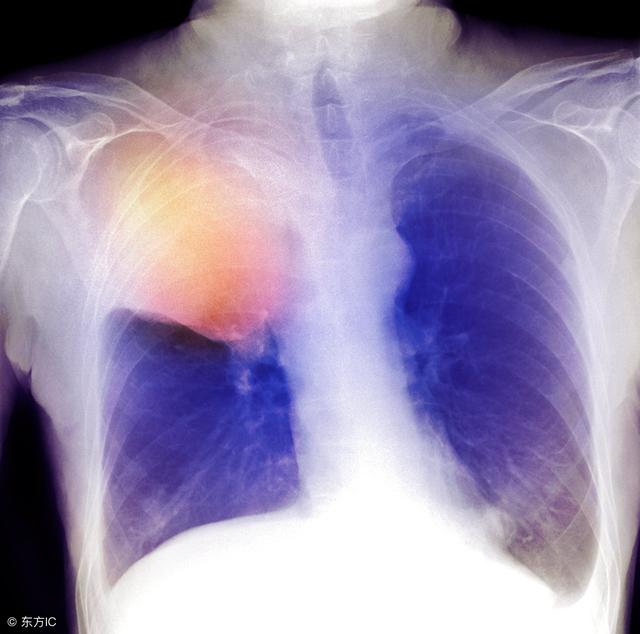

更多健康内容不再错过,不定期惊喜送给你近年来,肺癌发病人数在全球呈持续上升趋势,肺癌发病率占所有癌症发病率的12%。

当人们被宣告“肺癌”时,心中便是绝望,其实肺癌的最佳治疗方法并不是没有,关键看你有没有仔细寻找。医学技术发展迅速,对于众多疾病治疗均有攻克,例如肺癌。